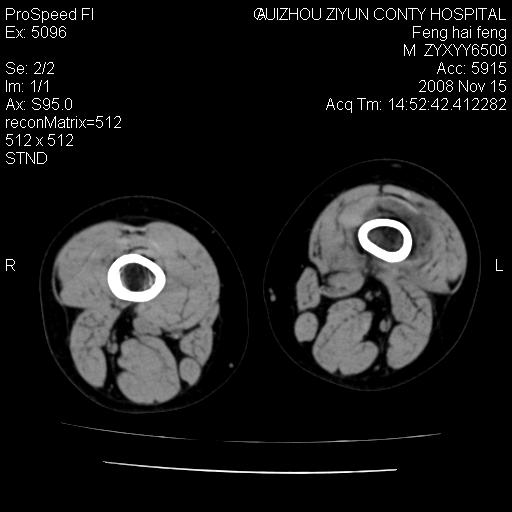

标题: CT16656:M 14Y 左膝关节肿胀一年余。其余病史不详。 [打印本页]

标题: CT16656:M 14Y 左膝关节肿胀一年余。其余病史不详。

考虑左侧髌骨结核;左膝关节滑膜肿胀、增厚,关节囊积液。

左膝滑膜型关节结核可能性大!支持!滑膜型关节结核主要ct表现:关节囊肿胀,积液,关节面见小破坏灶,并见点状死骨!

好大的左腿!考虑左侧髌骨结核,左膝关节滑膜肿胀、增厚,关节囊积液。

左侧髌骨结核;左膝关节滑膜肿胀、增厚,关节囊积液